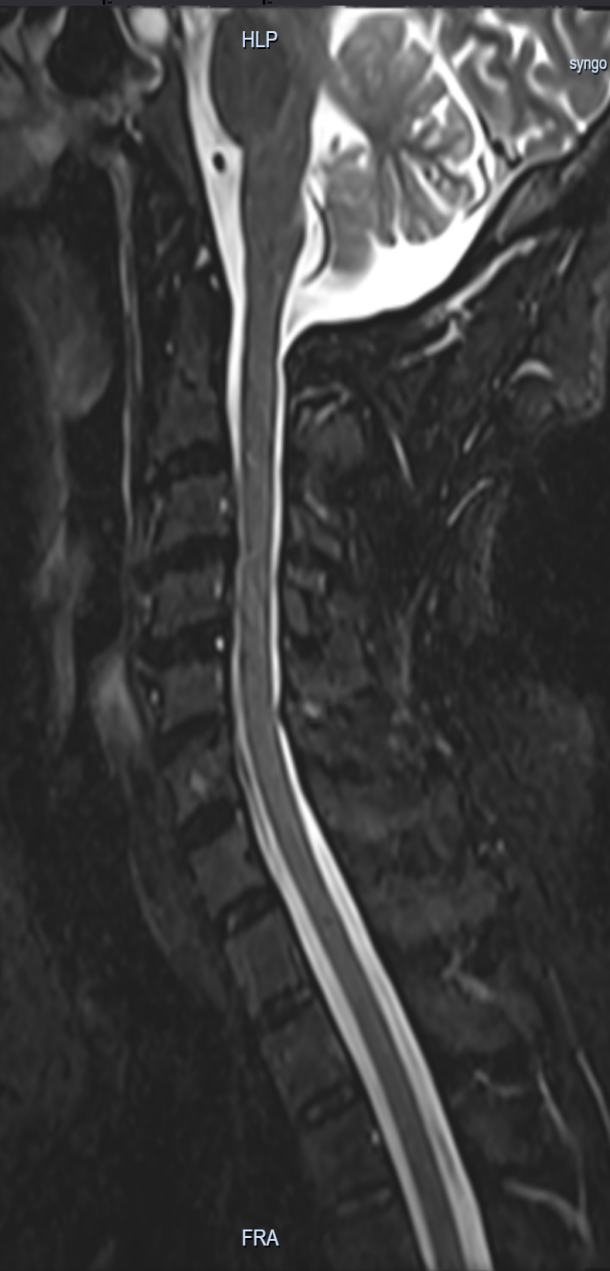

鉴于患者既往病史,首先需要排除动脉夹层复发并累及脊髓供血动脉的可能性,医院迅速开启绿色通道,立即安排主动脉强化CTA检查。

CTA显示:“胸、腹主动脉及双髂动脉粥样硬化

;主动脉弓降部支架术后;主动脉弓降部前方混杂密度灶,考虑假腔机化可能;降主动脉下段附壁血栓可能。请结合临床。”(见图1、图2)

图1

图2

报告并未明确支持新发的、活动的主动脉夹层,尤其是那种足以瞬间阻断多根脊髓根大动脉的广泛撕裂。同时,颅脑CT也未见急性出血或大面积梗死。